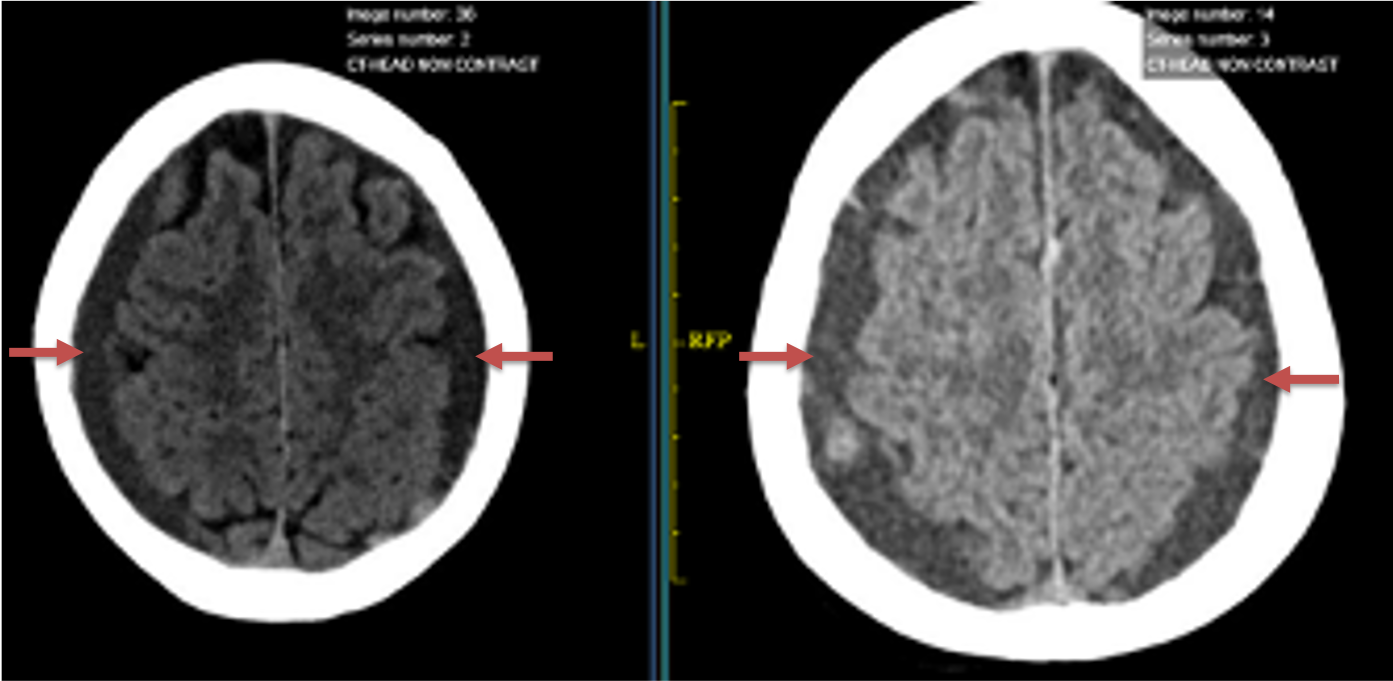

The patient agreed to receive minimally invasive treatment with Bilateral Middle Meningeal Artery Embolization, a new approach to promote resorption of chronic and subacute subdural hematomas in patients that are not improving with conservative measures or have contra-indications to surgical evacuation. Selective catheterization of the Middle Meningeal Artery is followed by transarterial embolization of the territory and inflammatory membranes that are felt to be secreting serosanguinous proteinaceous exceeding the capacity for resorption. MMA embolization was performed bilaterally in this patient. (Figure 2. A and B)

Figure 2. A) Initial right ECA angiogram ; B) Post MMA Embolization; C) Selective Embolization Of Middle Meningeal Artery Membranes using PVA particles (arrows)